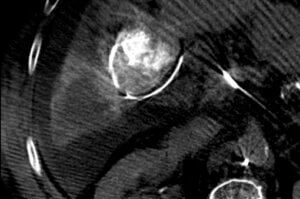

Mapping Angiogram

The mapping angiogram confirmed the presence of tumor hypervascularity arising from a small branch of the right hepatic artery.

Cone-beam CT

A cone-beam CT was performed during the mapping angiogram to better characterize the vascular anatomy of the tumor and identify any non-target enhancement of normal liver. A single feeding artery to the tumor was confirmed. This artery did not contribute blood supply to normal liver. On the treatment day, the tumor was treated via superselective administration of y-90 glass microspheres in a radiation segmentectomy approach.